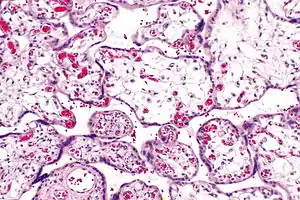

Placental villous immaturity

| Micrograph of villous immaturity. H&E stain. | |

Immature chorionic villi are larger and have more central blood vessels; thus, the diffusion distance for gas and nutrient exchange is larger and, therefore, placental function is impaired.